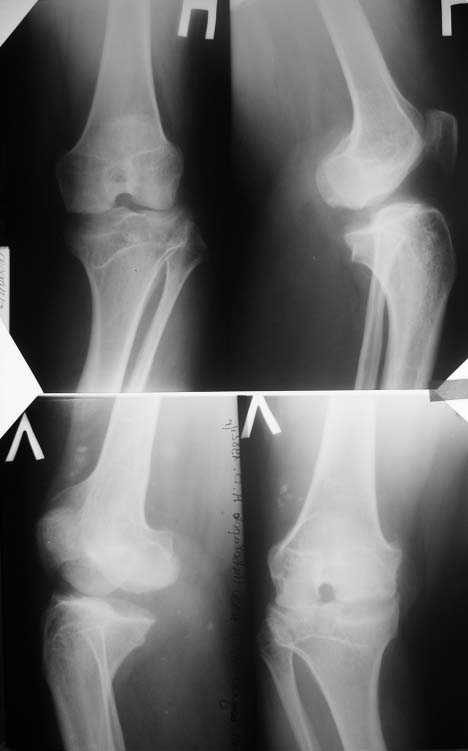

Прямая и боковая обоих коленных суставов

Вложение не в текстовом формате было извлечено…

Имя     : 3.jpg

Тип     : image/jpeg

Размер  : 29677 байтов

Описание: отсутствует

Url     : http://weborto.net:8080/pipermail/ortho/attachments/20090118/e452b84f/attachment-0005.jpg